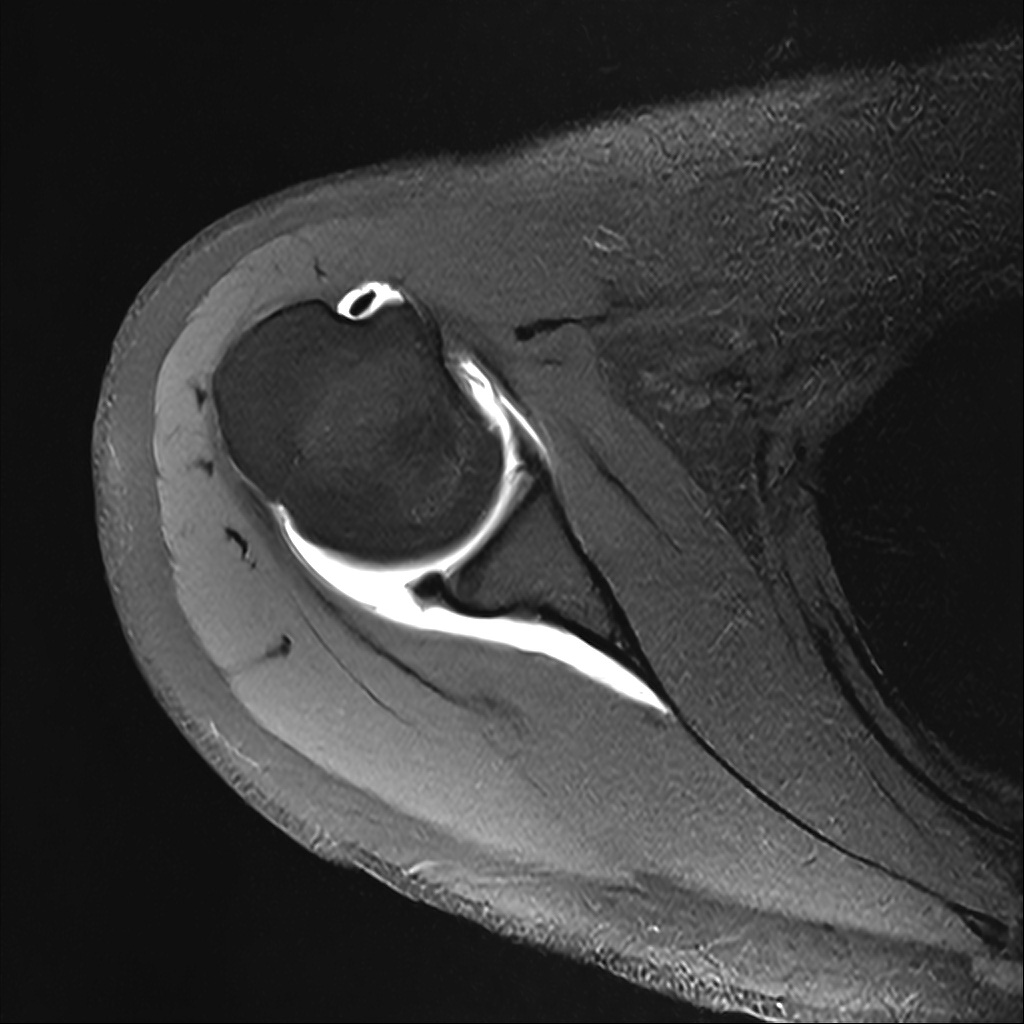

Mri 단면 영상으로 보아 어깨 관절 부위에서 이상 신호가 관찰되고 이는 관절 와순 파열의 가능성을 시사할 수 있습니다.

하지만 이영상만으로 정확한 진단은 불가능하고 정밀한 판단을 위해선 전체 시퀀스와 영상의학과 전문의의 공식판독이 필요합니다 특히 와순 파열은 위치와 동반 병변에 따라 해석이 달라집니다!